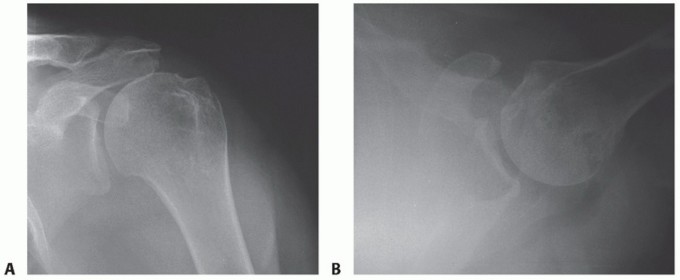

FIG 4 • Radiographic findings of degenerative arthritis, suggestive of a poor surgical candidate for an isolated superior latissimus dorsi transfer. However, this patient may be a good candidate for latissimus dorsi transfer to the lateral humerus in combination with reverse shoulder arthroplasty for rotator cuff tear arthropathy associated with an external rotation lag sign. A. True AP radiographic view of the glenohumeral joint showing osteoarthritic changes, osteophyte formation, and superior migration of the humeral head. B. Axillary lateral view of the glenohumeral joint showing osteoarthritis with early posterior glenoid wear.*

A true anteroposterior (AP) radiographic view of the shoulder in the plane of the scapula and axillary view is obtained (FIG 3A,B).

This allows evaluation of glenohumeral arthritis, superior migration of the humeral head, and identification of any abnormal bony anatomy (FIG 4A,B).